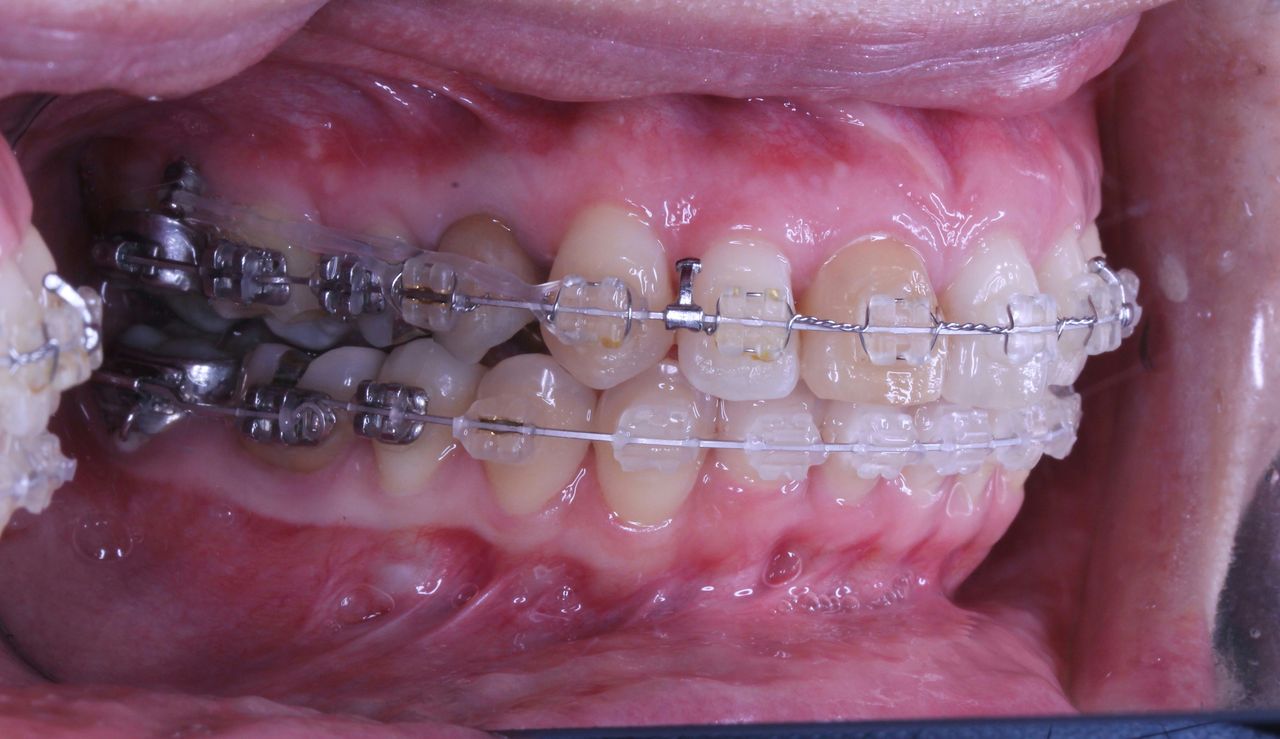

少し経過が進みました

治療開始から3年経過した現在の状況です